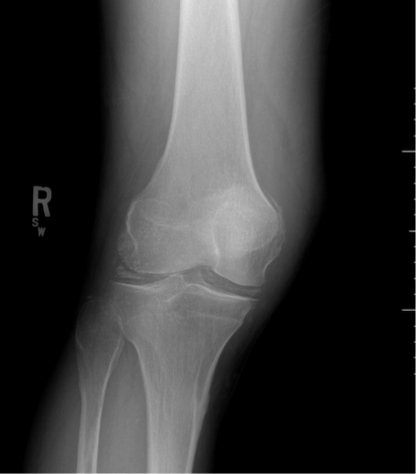

A 53-year-old male presented with worsening right knee pain and swelling over the past 48 hours. He denied recent trauma to the knee, history of IV drug use, and recent illness. He had no history of diabetes, immunodeficiency, chronic steroids, rheumatologic disease, or knee replacement. He described the pain as sharp, non-radiating, and worse with movement. He was unable to walk due to pain.

Radiographs of the knee showed multiple radio-dense lines paralleling the articular surface (see red arrows) consistent with calcium pyrophosphate crystal deposition within the joint often seen in calcium pyrophosphate disease (CPPD) also known as pseudogout.

Patients commonly present to the emergency department with non-traumatic joint pain. Arthrocentesis is an important diagnostic tool to evaluate for septic arthritis, gout, or pseudogout. Arthrocentesis can demonstrate crystals or abnormal cell count, gram stain, and culture.[1] In the evaluation of joint pain, plain films are usually obtained to evaluate for fracture, dislocation, effusion, or secondary signs of infection. In this case the classic x-ray supported the diagnosis of CPPD.2 The patient was found to have positively birefringent rhomboid shaped crystals consistent with pseudogout on arthrocentesis. Gram stain and culture were both negative. The patient was discharged with NSAIDs and had significant improvement in symptoms upon follow up with primary care physician in 3 days.